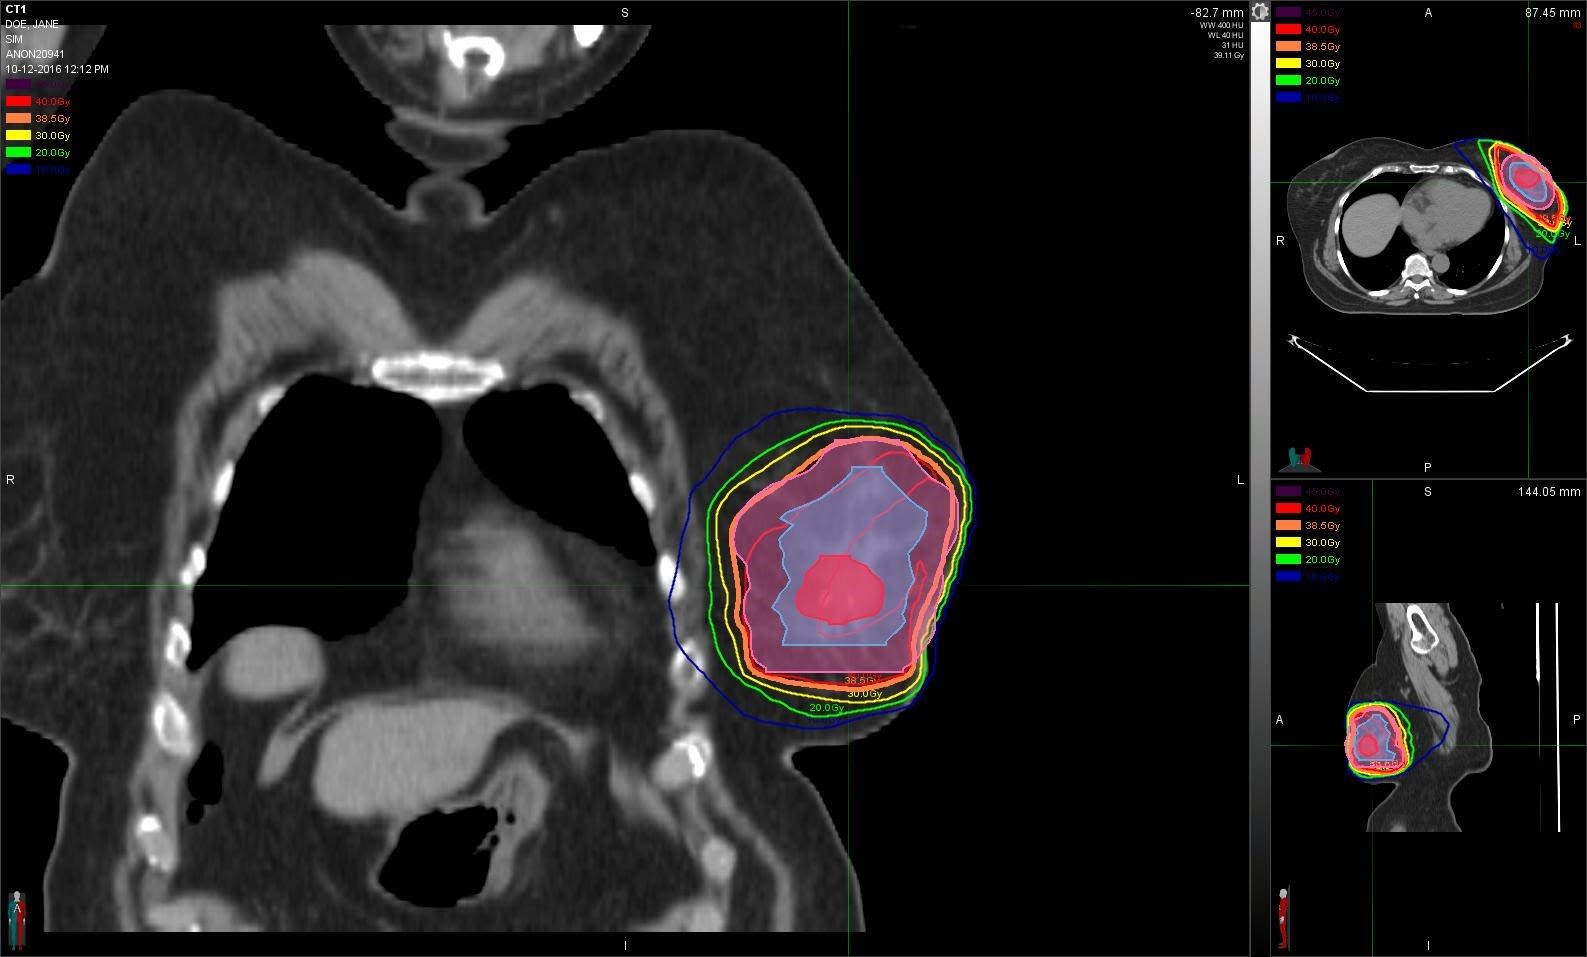

The colored portions of the scan represent the calculated area that gets radiated after breast conservation or lumpectomy. (Photos courtesy of Beth Anglin)